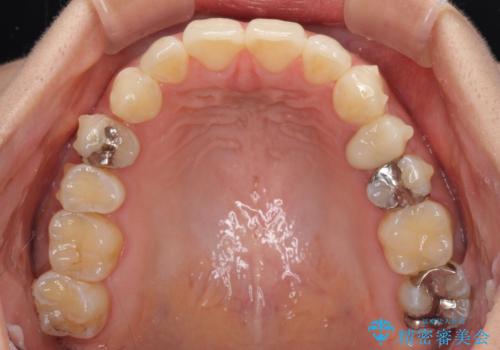

八重歯の再矯正 インビザラインでストレスなく矯正治療

- 学生の頃に矯正治療を行ったものの、保定を怠けてしまったことによる後戻りを気にして来院された患者様です。

根管治療が必要な歯があったため、矯正治療前に根管治療を行い、その後はインビザラインにより矯正治療を行うこととしました。

矯正治療後には根管治療を行った歯の補綴治療を行うこととしました。

下顎の八重歯が上顎歯列に収まる過程で咬みにくさがありましたが、最終的には、咬み合わせも安定し、きれいに歯列を整えることができました。